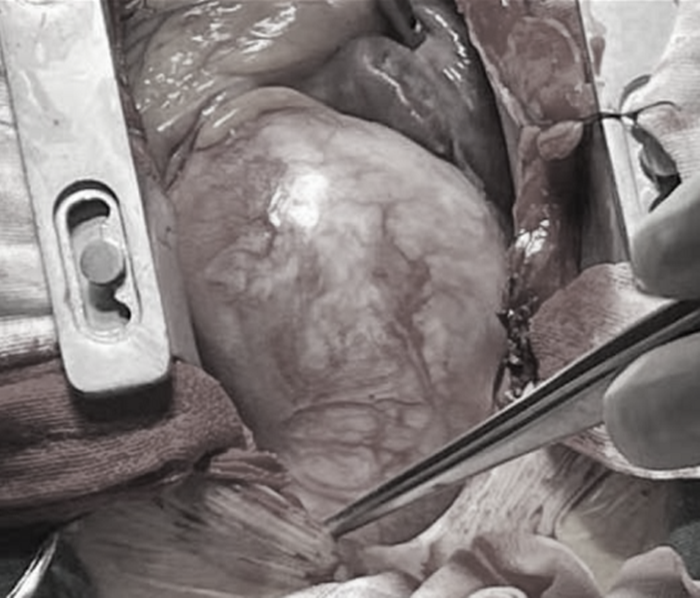

“David手術(shù)最大的特點就是保留患者的主動脈瓣膜,經(jīng)過一段時間的休養(yǎng),就可以和正常人一樣生活,不需要終身服用抗凝藥物。”在周珉的帶領(lǐng)下,心胸外科團隊為小吳順利實施David手術(shù),保留了主動脈瓣,完成了主動脈竇部再植。

手術(shù)前主動脈情況

手術(shù)后主動脈情況